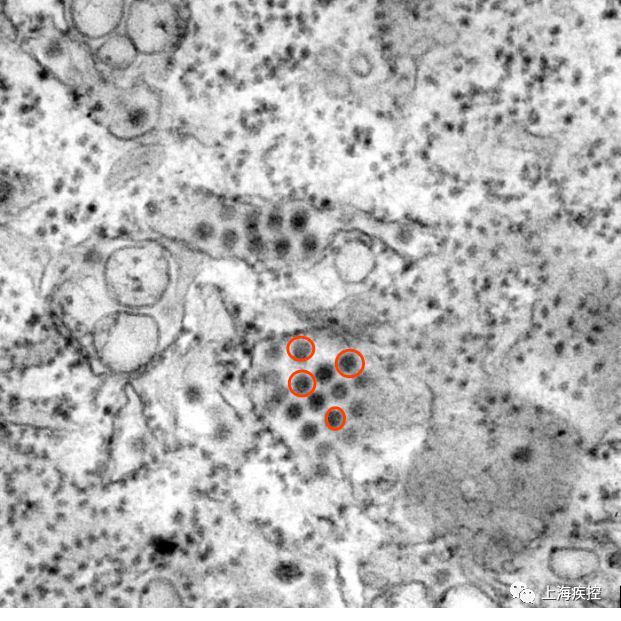

图1. 电镜下的登革病毒粒子

(图片来自美国CDC素材库)

我很渺小 , 小到单用肉眼根本看不见 , 但足以让人类发热、肌肉关节疼痛、出皮疹 , 得一种叫作“登革热”的病 , 甚至让人死亡 。